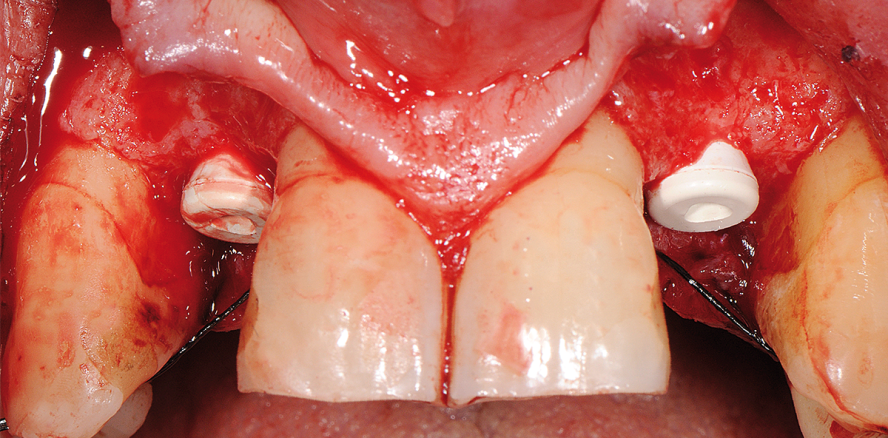

Nach lokaler Anästhesie erfolgte eine krestale, leicht palatinal versetzte Schnittführung mit jeweils nur einer bukkalen, nach distal angelegten Entlastungsinzision. Da das hier verwendete Implantat (ZERAMEX P6 Implantat) im Design kongruent zum Straumann SP Titan-Implantat ist, erfolgte die Insertion von zwei Implantaten mit je 4,1 mm Durchmesser und 12 mm Länge analog dem chirurgischen Protokoll (Straumann SP Implantat) innerhalb der Komfortzone:27 Implantatschulter 2 mm unterhalb der Schmelz-Zement-Grenze der Nachbarzähne, leicht palatinal versetzt mit einer für eine palatinale Verschraubung geeigneten Achsneigung. Diese tiefe Positionierung der Implantatschulter ist nur möglich, da das Implantat zementfrei verschraubbar ist (Abb. 6–8b).

An beiden Implantatpositionen wurde eine laterale Konturaugmentaton (Bio-Gide, Bio-Oss) durchgeführt. Unter anderem dient dies zur Vermeidung von Rezessionen, welche durch das auch bereits bei SP Implantaten beschriebene, trichterförmige, aber stets stabile Bone Remodeling entstehen könnten.28 Um einen möglichst spannungsfreien Wundverschluss zu erreichen, wurde die Kollagenmembran gelocht und über das Implantat gezogen (Abb. 9 und 10). Nach Periostschlitzung konnte das Operationsgebiet bakte­riendicht vernäht werden. Der Heilungsverlauf war komplikationslos.

Bei der Implantateröffnung zwölf Wochen post OP zeigte sich über dem Implantat 12 eine leichte, vollkommen reizlose Perforation (Abb. 11). Der Gingivaformer konnte hier daher ohne weitere Maßnahmen eingebracht werden (Abb. 12). Das Implantat 22 war vollständig bedeckt und wurde mit ­einem bukkal gestielten Roll-Flap eröffnet (Abb. 13).